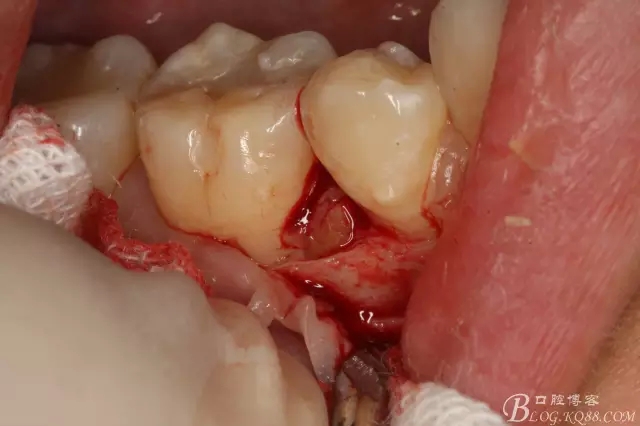

圖8.高速球鉆去骨約3mm.

圖9.暴露45頰側(cè)根面約1/2.牙根與44、46牙根緊緊相鄰。無法直接用挺。

圖10.高速裂鉆垂直分根